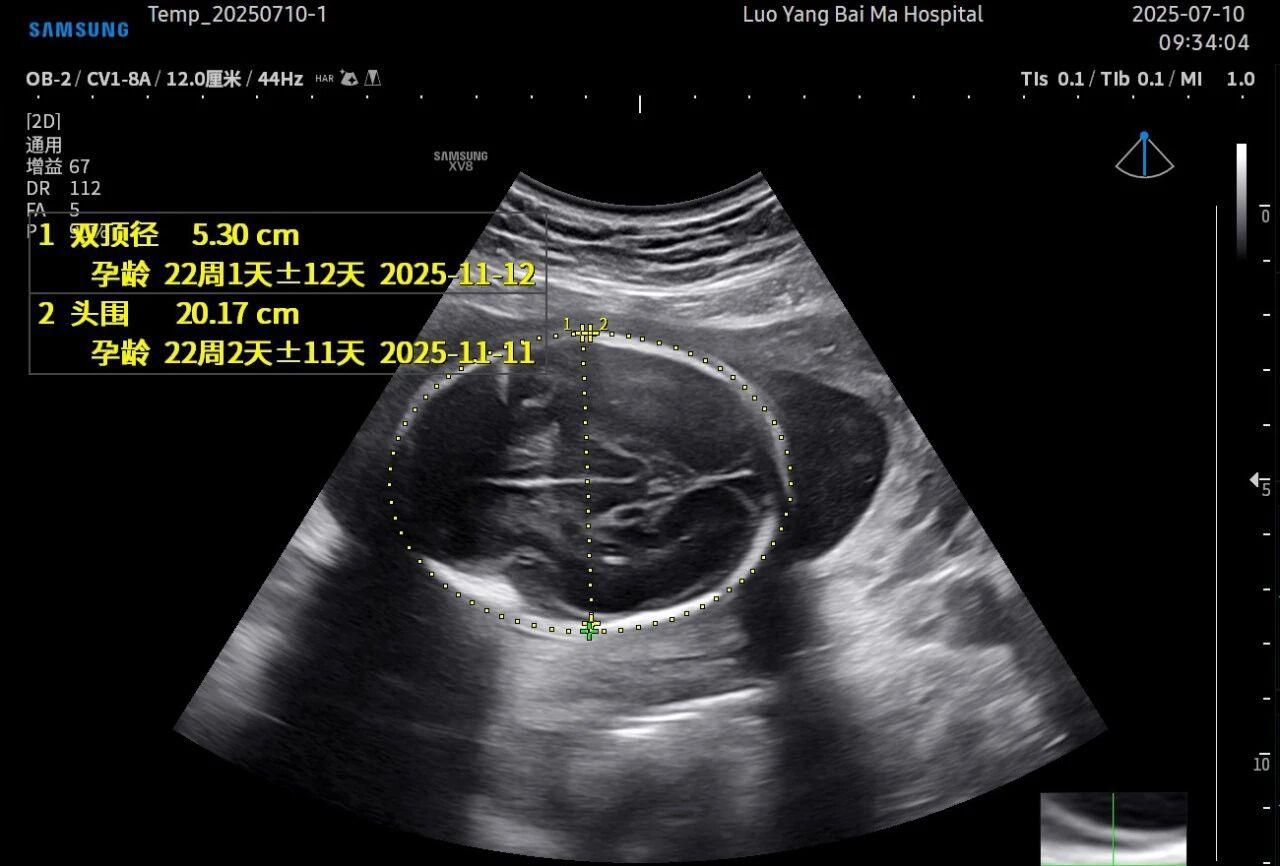

这是5D技术的核心优势之一。系统内置了强大的智能化大数据分析功能和AI辅助诊断工具。例如,在进行胎儿颈项透明层(NT)测量、胎儿长骨(LB)测量等关键生物学指标评估时,5D智能系统可以自动识别解剖层面、智能勾勒测量范围并进行计算。这不仅大大缩短了检查时间,更重要的是,它通过标准化的智能算法减少了因人为操作可能产生的误差,使诊断结果更加客观、可靠。

• 5D彩超检查通常建议在孕20-26周,尤其推荐在孕22-24周进行。此时胎儿大小适中,羊水量充足,图像清晰度较高。